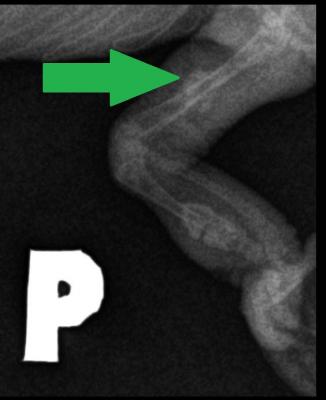

5 týdnů po zákroku již byla kost plně srostlá. Místo původní zlomeniny ukazuje největší zelená šipka. I ostatní zlomeniny, kde fragmenty nebyly dislokované, se zpevnily pomocí svalků - což jsou chrupavčitokostěnné zduřeniny (pomocí nichž se spontánně hojí nedislokované fraktury), znázorněné na snímku zelenými šipkami (když si na obrázek kliknete, tak se Vám zvětší a můžete si vše detailně prohlédnout).

Zvětšený výřez, kde jde vidět, jak se fraktura krásně zahojila.